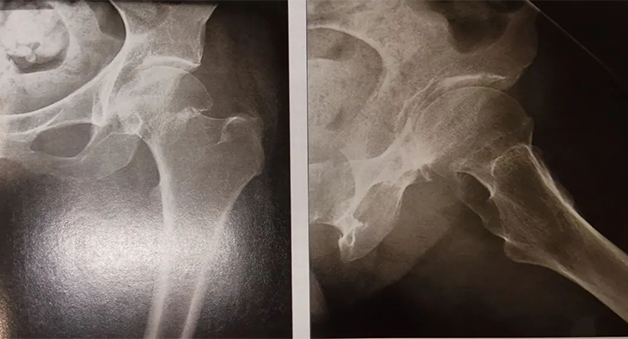

股骨近端骨折桥接内固定术

股骨近端骨折即股骨粗隆下骨干部分的骨折,股骨近端骨折的分类不一,从预后及整复难度分析,可分为下列各类型:

④粉碎骨折根据各个骨块情况决定整复与内固定次序。一般合并应用螺钉与钢板。此型骨折的治疗主要采用钉板内固定。